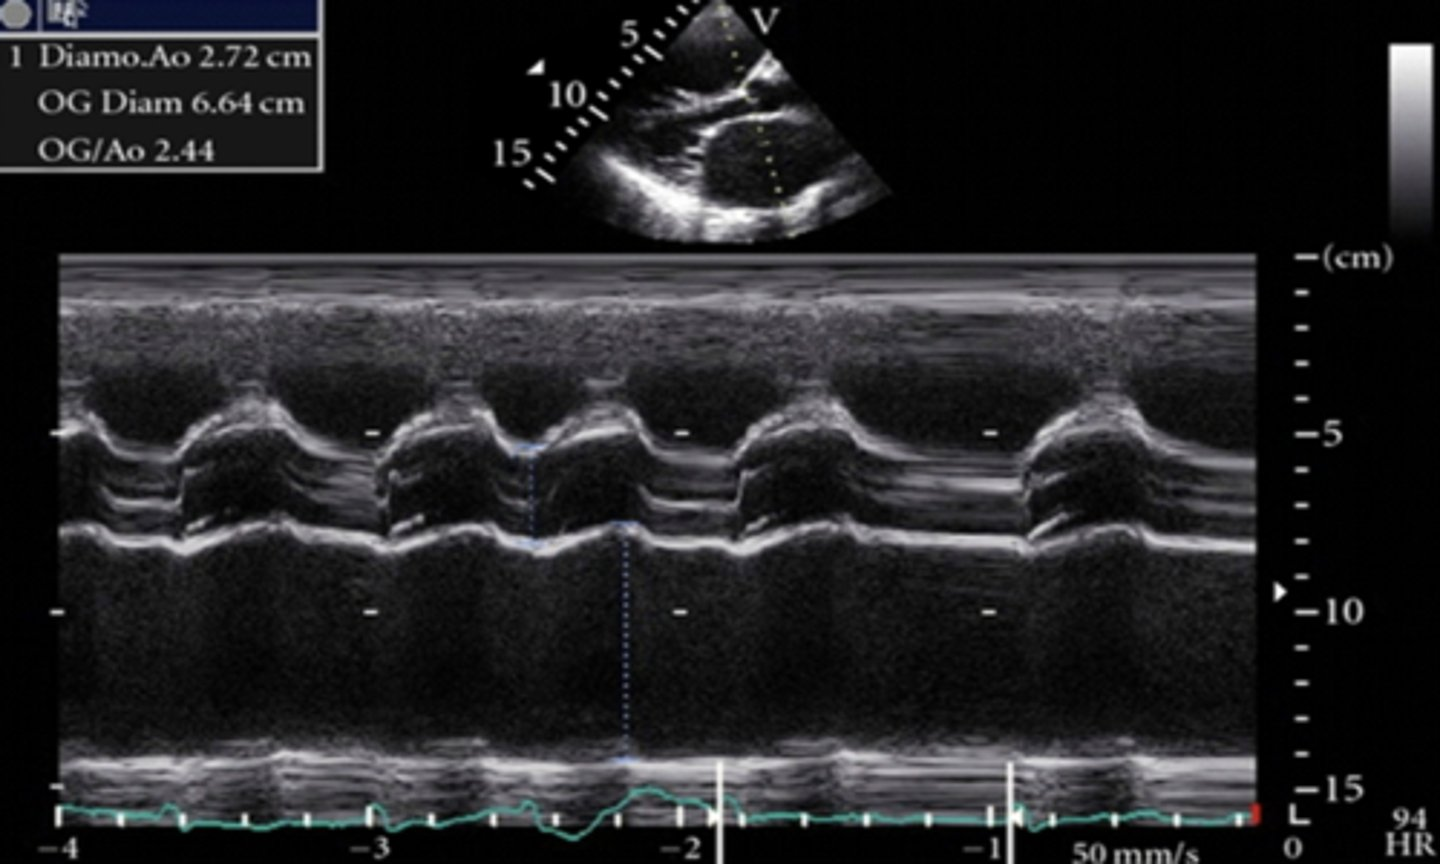

larger than 1:1 ratio between LA and AOR with larger LA

dilated left atrium

a dilated left atrium is caused by _________, _______, _______, ________, or ________________

mitral regurgitation, mitral stenosis, significant LVEDP, mitral valve prolapse, and chronic severe aortic insufficiency

larger than 1:1 ratio between LA and AOR with larger AOR

dilated aortic root